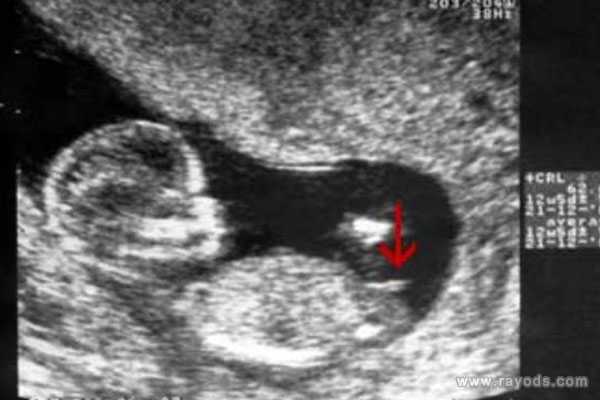

(女孩的nt图片)

13周nt图中男女特征是非常明显的,很多人都觉得这个时候孕周还小,胎儿还未正式开始发育。尽管如此,但在很多过来人看来,这个时候的nt图中男孩女孩已经有了区别了,胎儿身体姿势就已经给了暗示。

首先看nt图中胎儿整个身体的幅度,如果身子是弯着的,说明怀的是男孩,反之如果身子是平行的,则怀女孩,据说很多人都是根据这一点对比男女的不同的。

再者就看胎儿脊柱线和尾椎骨,按照男孩女孩发育的不同,男孩的脊柱线会大于30度甚至更多,身体明显有弯曲的弧度,而女孩的脊柱线一般都是小于30度的,看起来就是平缓的睡在妈妈肚子里。就对于这一点,老人们也有一个说法与之类似,那就是儿靠女睡,其意思就是儿子靠着妈妈,女儿则睡在妈妈肚子里。

最后就看胎儿的尾椎骨这里了,据说胎儿尾椎骨上翘的话则说明怀的是男孩,反之如果尾椎骨和身体保持平行的话则生女孩。尾椎骨是男女特征最大的区别点,因为这个地方是要发育生殖器的,尤其是男孩尾椎骨会上翘,这是在给生殖器发育留下空间,因此才会有这个姿势。

就根据以上说到的三个特征对比可以看出,男孩女孩之间的区别还是很大的,一个是nt图的姿势、一个是脊柱线大于小于角度,另一个就是尾椎骨上翘和平行,看起来好像的确很准确,但这是不是真的准呢?这一点就说不准了,其实这些所谓的方法都是已生宝妈们的所谓的经验总结,大家结合参考下就行了,不要太执念于结果。